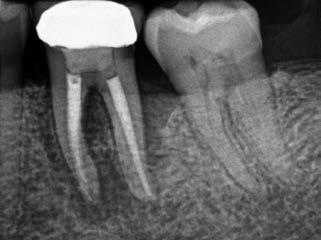

2. ábra: A hat hónapos kontroll alkalmával készített röntgenfelvételen vastag dentinhíd látható a pulpasapkázó anyag alatt.

3. ábra: A hároméves kontroll alkalmával készített röntgenfelvételen megfigyelhető a restaurátum pontos illeszkedése.

A diagnózisunk reverzibilis pulpitis volt. Periapicalis elváltozás jelenlétét nem vélelmeztük. A fogban lévő amalgámtömés eltávolítása során körülbelül egy 3 mm átmérőjű pulpaseb keletkezett a buccalis pulpaszarvnak megfelelően (1. a–g. ábrák) Mivel nem tapasztaltunk jelentős vérzést, és a diagnózisunk reverzibils pulpitis volt, ezért a direkt pulpasapkázás elvégzése mellett döntöttünk.

A kavitást 2,5%-os nátrium-hipoklorit oldattal fertőtlenítettük, majd sűrű konzisztenciájú kalcium-szilikát alapú anyagot (CeraPutty, Meta Biomed) készítettünk elő a direkt pulpasapkázás elvégzéséhez. Az első kezelés végén röntgenárnyékot nem adó ideiglenes töméssel (NexTemp LC, Meta Biomed) zártuk

az üreget annak érdekében, hogy a direkt pulpasapkázásra használt anyag megfelelő pozícióját radiológiailag ellenőrizni tudjuk. A második ülés során kompozit tömőanyagból (Ezfil, Meta Biomed) direkt adhezív restaurátumot készítettünk.

A kezelést követően a beteg tünetmentes volt. A kérdéses fog a kontrollvizsgálatok során végzett szenzibilitástesztekre fiziológiás reakciókat adott. A hat hónapos kontroll alkalmával készített röntgenfelvételen a sérülésnek megfelelően széles dentinhidat észleltünk (2. ábra). A restaurátum a hároméves kontroll során is megfelelőnek bizonyult (3. ábra)